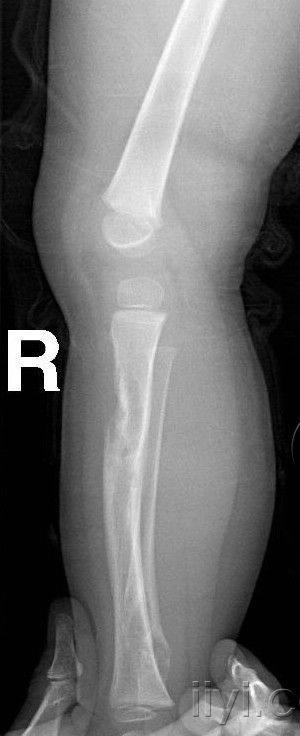

以下是引用zhangzhongshou在2007-5-26 22:17:00的发言:[br]腓骨下端、胫骨中段骨质膨胀改变,胫骨有骨硬化,多考虑胫腓骨骨纤维异常增殖症,伴腓骨病理性骨折。

以下是引用dongjianchun在2007-5-27 12:59:00的发言:[br]胫腓骨噬酸性肉芽肿